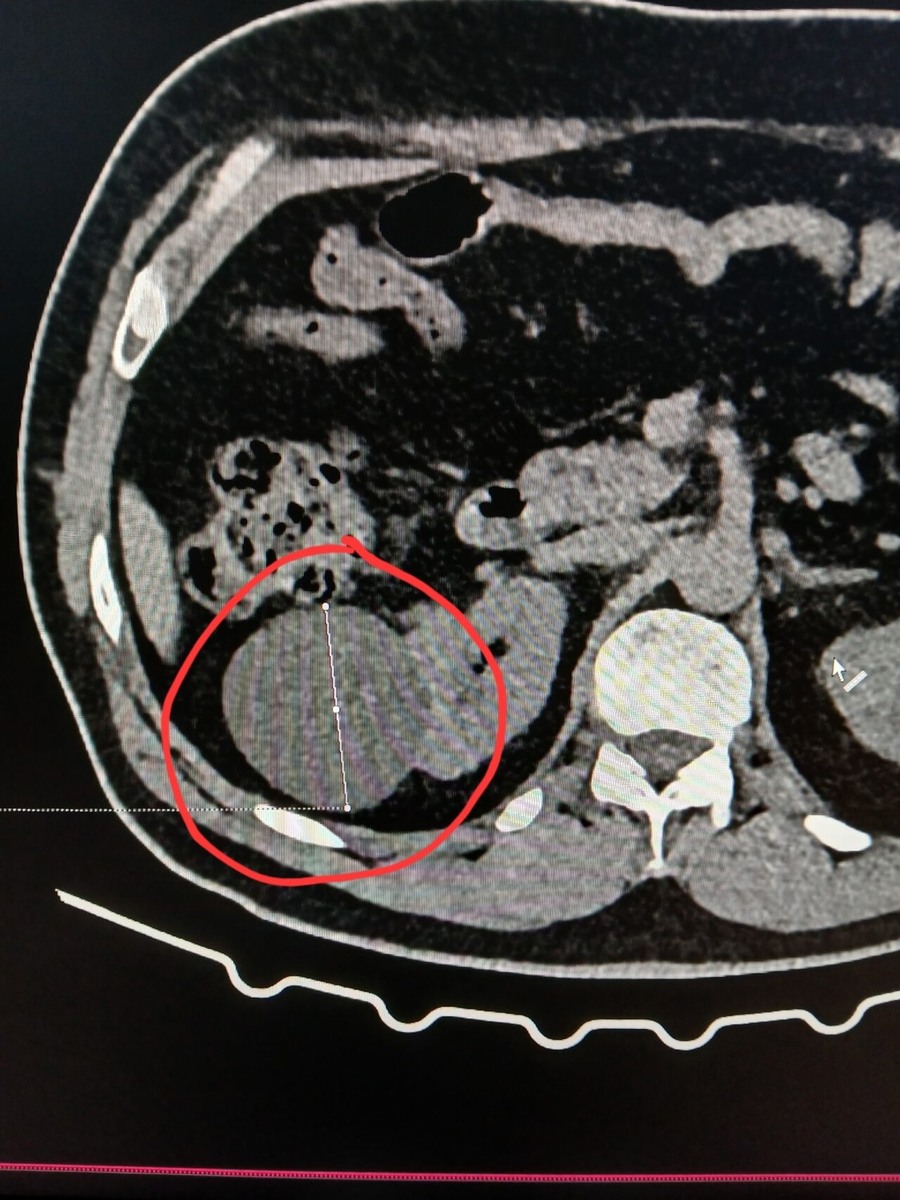

Киста почки при компьютерной томографии визуализируется как объемное жидкостное образование округлой формы с четкими ровными контурами. Ключевым диагностическим критерием является характеристика ее содержимого и поведение при контрастном усилении.

Простая киста имеет однородное содержимое с плотностью, характерной для жидкости, не накапливает контрастное вещество и обладает тонкой, невидимой стенкой. Это доброкачественное образование.

Сложные кисты требуют особого внимания, отметил министр. Их признаки включают наличие перегородок, утолщение стенок, кальцинаты и, что наиболее важно, усиление этих элементов после введения контраста. Последнее указывает на васкуляризацию (кровоснабжение) тканей и является маркером потенциальной малигнизации (возможности озлокачествления), что диктует необходимость дальнейшего наблюдения или хирургического вмешательства.